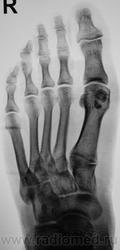

Пол пациента: Женский пол Тип патологии: Травма Область исследования: Скелетно-мышечная система Методы исследования: Rg Пациент направлен по поводу травмы. Случайная находка... https://radiomed.ru/sites/default/files/styles/case_slider_image/public/user/12/2.201310200016.jpg?itok=VzEdq3KK https://radiomed.ru/sites/default/files/styles/case_slider_image/public/user/12/3.201201010012_2.jpg?itok=US4gX77V https://radiomed.ru/sites/default/files/styles/case_slider_image/public/user/12/4.201310200014.jpg?itok=l6zzwcyf ID:32564 Пнд, 21/10/2013 - 23:57 #1 И.Бондаренко Не на сайте Был на сайте: 4 дня 2 часа назад Зарегистрирован: 13.09.2011 - 22:55 Публикации: 9206 И что это? Такое встречается, описываю как участок склероза или внимания не обращаю. Втр, 22/10/2013 - 16:54 #2 Pilulia Не на сайте Был на сайте: 7 лет 9 месяцев назад Зарегистрирован: 02.09.2011 - 14:27 Публикации: 14 или добавочная сесамовидная кость, как вариант.. Втр, 22/10/2013 - 22:16 #3 Катенёв Валенти... Не на сайте Был на сайте: 7 лет 2 недели назад Зарегистрирован: 22.03.2008 - 22:15 Публикации: 54876 Pilulia wrote: или добавочная сесамовидная кость, как вариант.. Добавочная? Сесамовидная?

И что это? Такое встречается, описываю как участок склероза или внимания не обращаю.

или добавочная сесамовидная кость, как вариант..

Добавочная?

Сесамовидная?